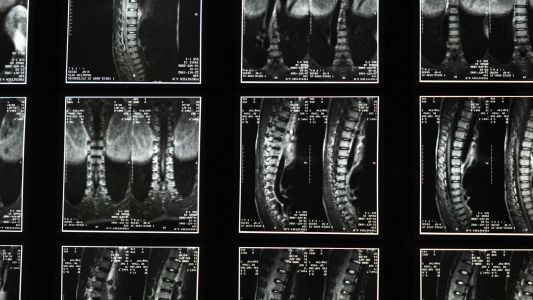

MR koristi magnetno polje i radio talase za detaljne slike tela, bez zračenja. Traje 30-60 minuta i efikasna je za otkrivanje anomalija mozga, tumora, srčanih problema i više.

Magnetna rezonanca kičme uz savremenu opremu i brzo zakazivanje. Idealno rešenje za bol, slabost ili trnjenje u leđima i udovima.